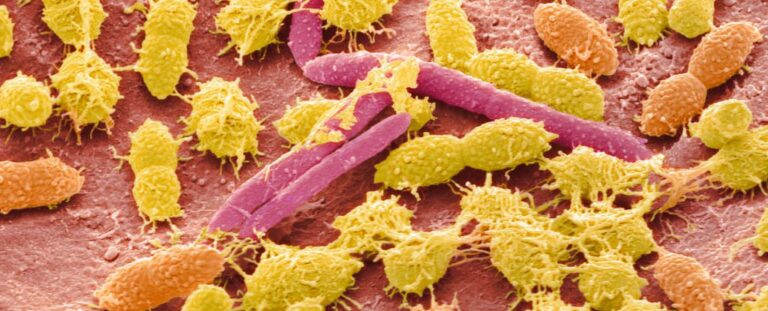

Obeliszk: az élet egy teljesen új formáját fedezték fel az emberi emésztőrendszerben

A most felfedezett obeliszk egyik biológiai ágensre sem hasonlít, és eddig valószínűleg azért nem figyeltek fel rá, mert nagyon kicsi. Egy adathalmazban az emberi szájminták felében is megtalálták.